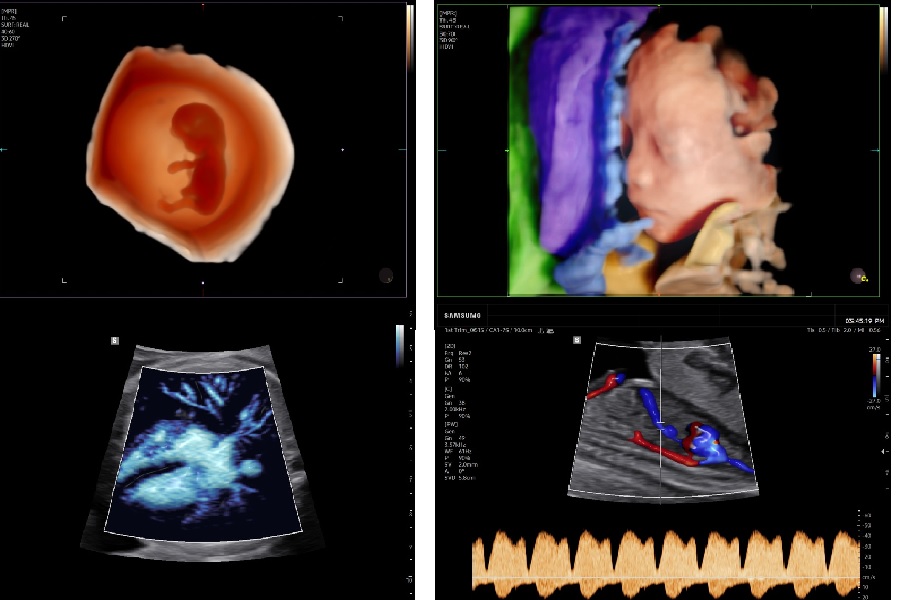

- Расширенные 3D/4D-режимы с AI-модулями для OB/GYN, MV-Flow и LumiFlow

Система самостоятельно проводит 46 измерений по 39 стандартным срезам, оценивая качество в реальном времени с помощью Live ViewAssist. Это ускоряет обследования и минимизирует ошибки.

3D/4D визуализация PortraitVue реконструирует реалистичное лицо плода из 3D-данных, создавая естественные черты для диагностики и фото для родителей.

- Сердце плода. Автоматические измерения в B-, M- и спектральных режимах: размеры желудочков, толщина стенок, функциональные показатели и ЧСС. Система 5D Heart Color и HeartAssist™ определяет стандартные срезы и выполняет измерения в автоматическом режиме.